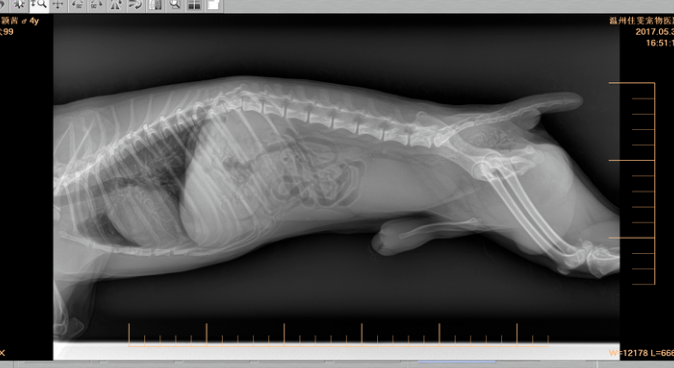

之后获知你的信息,离我们家很近的监管里发觉,狗狗在十二月十一日出车祸了,始终地离开我。